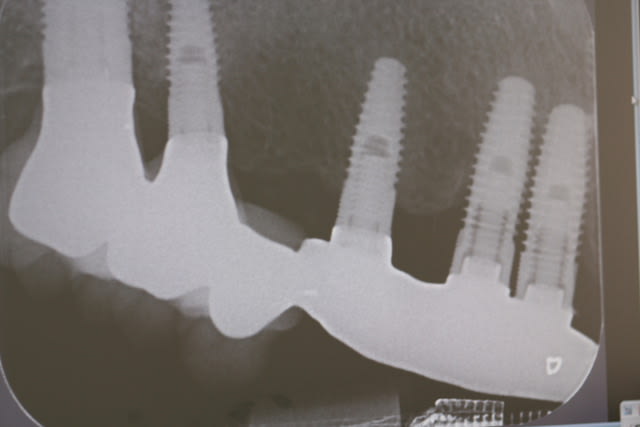

bridge en place depuis plus de 8 ans, assymptomatique, pas de mobilité, à la palpation on les sent sous muqueux

si le patient est content moi je suis content, il ne m'a rien demandé je ne lui ai rien dit

C'est beau de faire des chirurgies flapless !!!

même pas il décollait des lambeaux pour les mettre